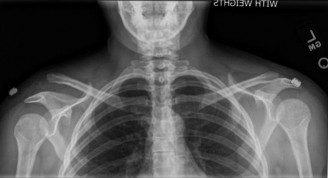

While the clinical examination provides a robust working diagnosis, advanced imaging is paramount for surgical templating, prognosticating, and definitively ruling out concomitant intra-articular or osseous pathology. The initial imaging modality must always be a high-quality, orthogonal radiographic series of the shoulder, including a true anteroposterior (Grashey) view, a scapular Y view, and an axillary lateral view. In a 76-year-old with a partial-thickness rotator cuff tear, radiographs may appear surprisingly benign.

However, subtle radiographic clues often hint at the underlying pathology. The Grashey view is scrutinized for the acromiohumeral interval (AHI). A normal AHI is between 7 and 14 mm. An AHI of less than 7 mm is highly indicative of a massive, chronic full-thickness rotator cuff tear allowing superior migration of the humeral head due to the unopposed upward pull of the deltoid. In our patient with a partial tear, the AHI will likely be preserved, as the intact portion of the cuff continues to depress the humeral head. We also evaluate the greater tuberosity for sclerosis, cortical irregularity, or cystic changes—the so-called "footprint cysts" that develop secondary to chronic micro-avulsions and hypervascularity at the tendon insertion.

The scapular Y view and supraspinatus outlet view are essential for evaluating acromial morphology. Bigliani classified acromial shapes into three types: Type I (flat), Type II (curved), and Type III (hooked). A Type III hooked acromion significantly decreases the subacromial volume and is highly correlated with an increased incidence of rotator cuff tears, acting as a relentless mechanical abrading force against the bursal surface of the supraspinatus tendon. Additionally, the axillary view helps assess for glenohumeral osteoarthritis and ensures the humeral head is concentrically reduced, ruling out chronic subtle dislocations.